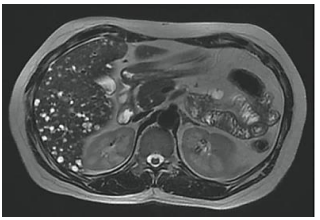

Analise a imagem de ressonância magnética ponderada em T2 e assinale o diagnóstico mais provável: